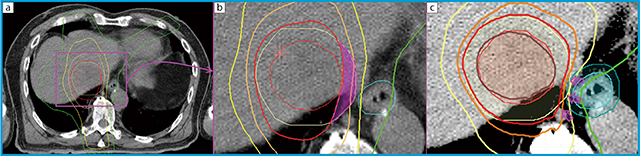

図2 肝細胞がんに対するSBRTの線量分布の一例(食道近接例)

a,bは,初回治療時の多軌道回転原体照射+固定照射による線量分布である。病巣が食道に近接しているため,食道への高線量照射を懸念して,食道近傍のPTVへの線量投与が不十分となった。この症例は1年を待たずに局所再発させてしまった。cはRapidArcにて再計画を行った線量分布図である。食道近傍まで高線量投与が可能である。この線量分布で照射をしていれば再発させないですんだかもしれない。悔やまれる症例である。 内側の○:GTV,○:PTV,等線量曲線は外側より10Gy(○),20Gy(○),30Gy(○),40Gy(○)(処方線量),45Gy(○)。